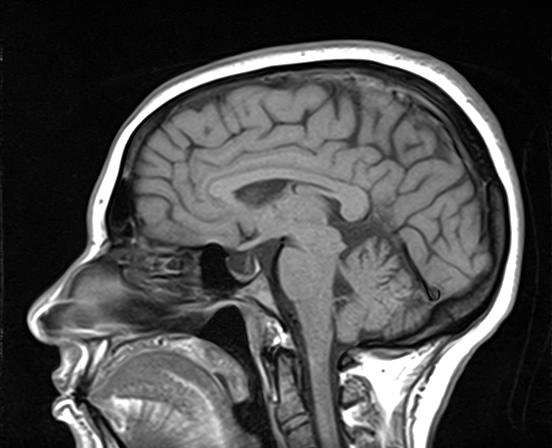

Schwannoma dây thần kinh hàm dưới (Masticator Space CNV3 Schwannoma)